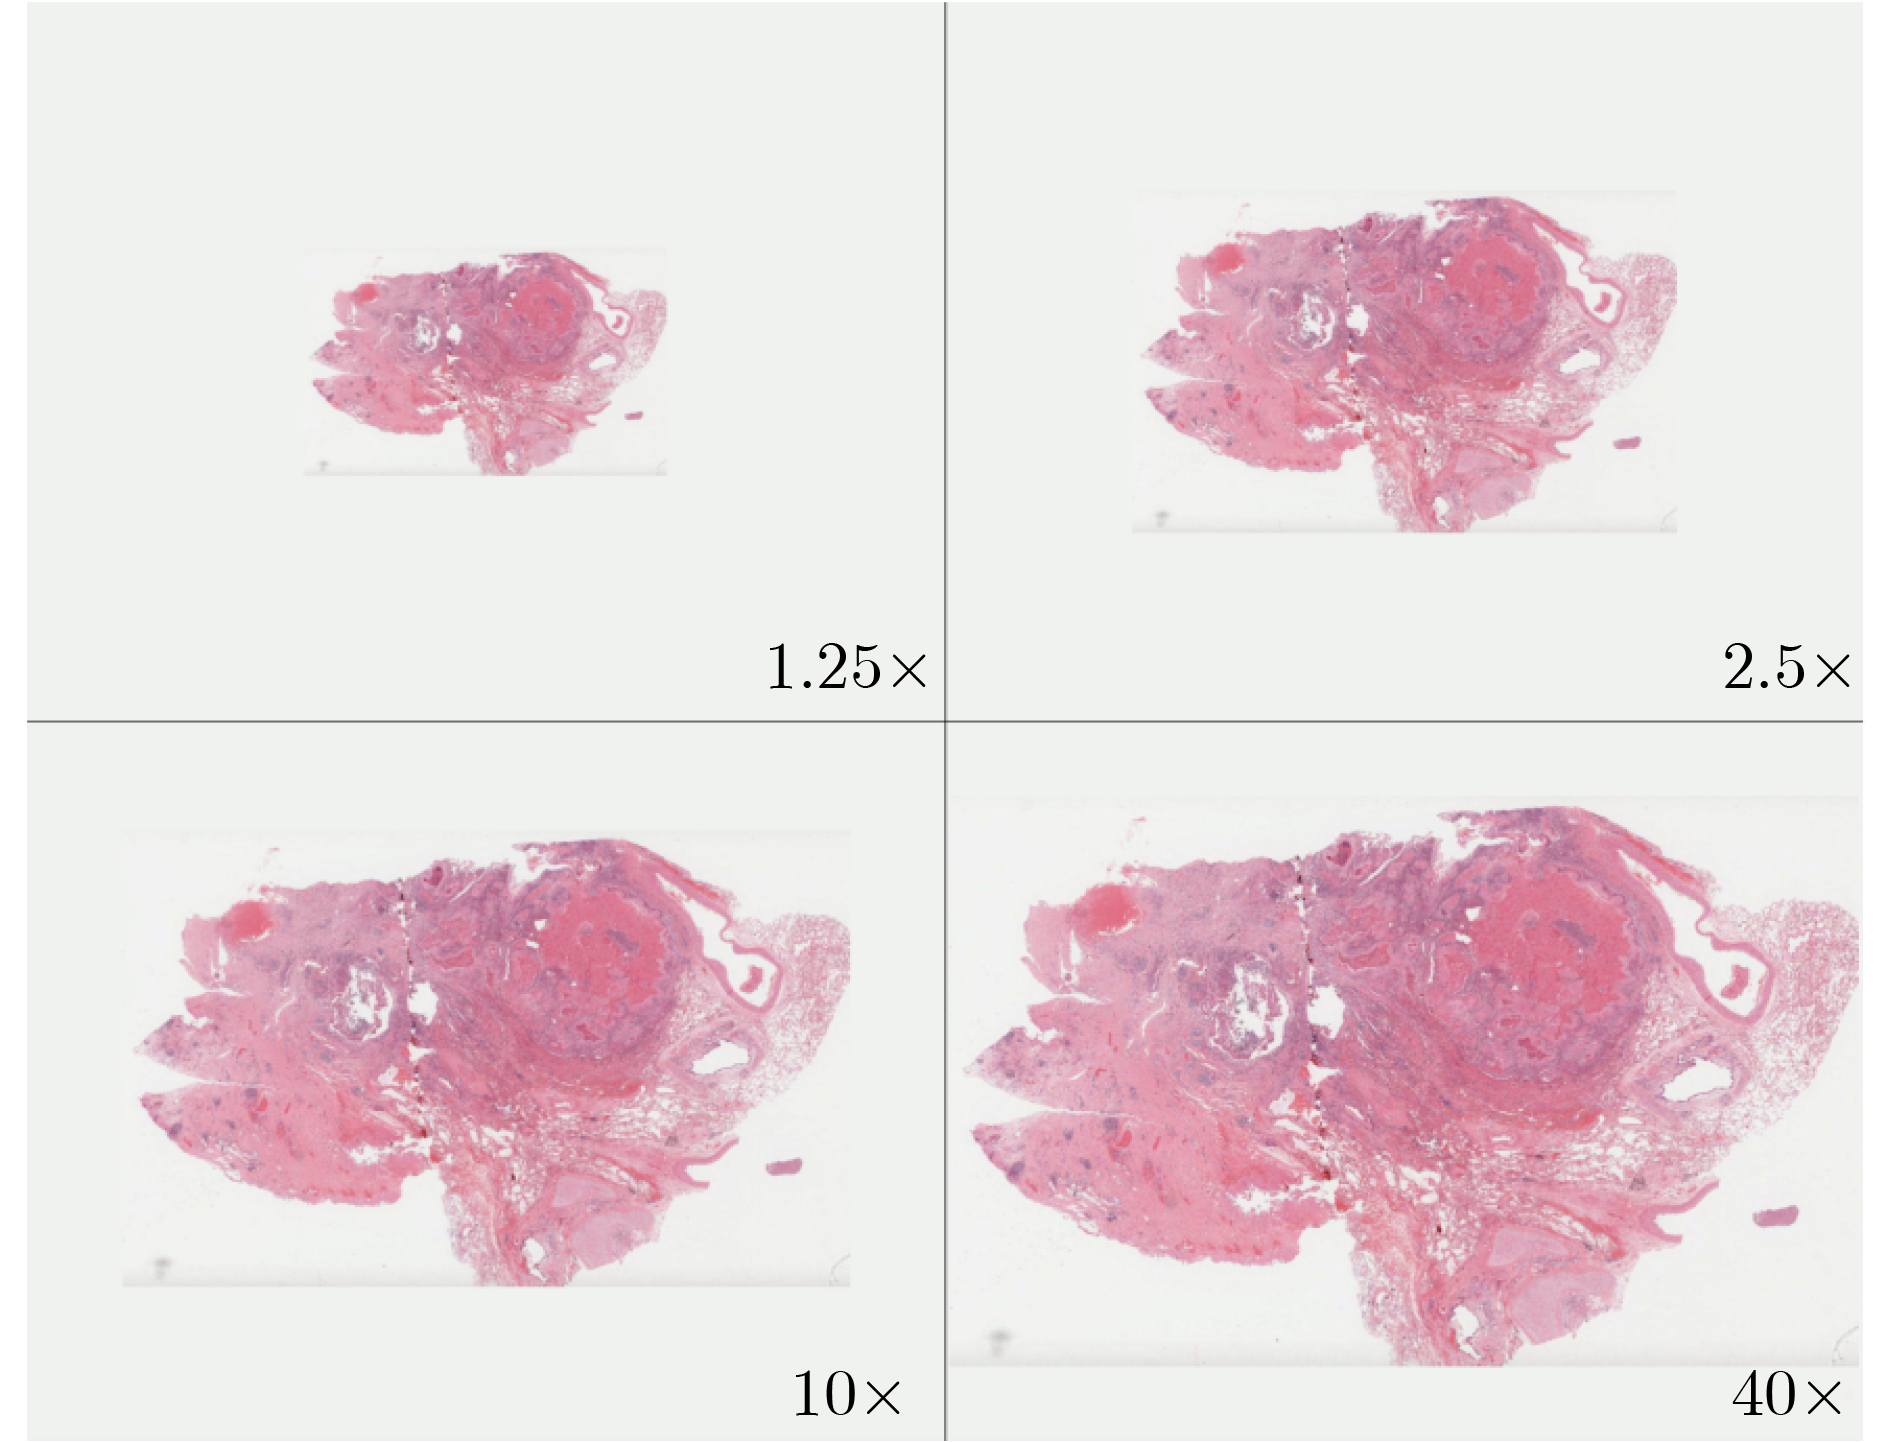

面向病理图像弱监督分类的层级融合多实例学习方法

陈晓禾, 张甲昂, 李玲芝, 李桂秀, 欧紫蓉, 鲍月华, 刘欣欣, 虞秋辰, 马雨涵, 赵可喻, 白华

2026, 48(3): 1116-1127. doi: 10.11999/JEIT250726

摘要:

病理图像分类对于癌症诊断至关重要,但现有方法存在依赖随机采样、多层级信息利用不足等问题。为此,该文提出一种层级融合多实例学习方法。首先,对病理图像的不同层级进行切分并用ResNet-50提取特征;然后,针对伪包标签不准确及背景噪声问题,提出基于注意力评价函数的伪包划分方法,利用门控注意力对低分辨率特征进行重要性评估,依据得分将特征划分为低分辨率伪包,并通过索引映射得到对应高分辨率伪包;最后,针对多层级信息利用不足的问题设计两阶段分类模型,第1阶段对低分辨率伪包进行初步分类,并依据预测置信度筛选出高判别性的关键区域及其对应的高分辨率特征;第2阶段通过交叉注意力机制,将筛选出的低分辨率特征与对应的高分辨率特征进行深度融合,随后将其与经过门控注意力聚合的高分辨率伪包特征进行拼接,以利用局部细节结合全局信息进行分析。在训练过程中,采用双分支交叉熵损失函数,联合优化低分辨率初步分类任务与高分辨率最终分类任务。实验使用了两个公开数据集Camelyon16, TCGA-LUNG及一个私有皮肤癌数据集NBU-Skin对模型进行测试,结果表明,该方法在多中心公开数据集和私有数据集上性能均优于CLAM, TransMIL等算法,其中在NBU-Skin数据集上5折交叉验证的平均准确率达到90.5%,平均AUC达到0.976。此外,该方法在跨病种、跨中心数据中表现稳定,为癌症病理的人工智能诊断提供了新的思路。